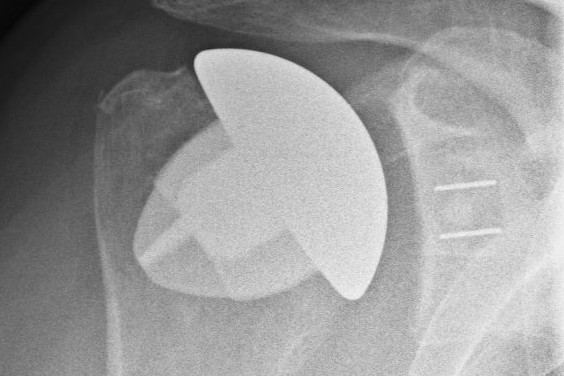

Ersatz des Schulter-, Knie- und Hüftgelenks (TEP)

Die 3 großen Gelenke des Körpers, die Schulter, das Knie und die Hüfte sind leider häufig durch Abnutzung oder nach Unfällen verschlissen. Wenn die konservativen Behandlungsmethoden nicht die gewünschte Linderung bringen, ist manchmal ein Gelenkersatz indiziert.

In unserer Praxis werden von PD. Dr. D. Böhm, Frau Dr. D. Böhm alle modernen Formen der Schulterendoprothetik eingesetzt um für Sie das beste klinische Ergebnis zu erzielen. Ortho-Mainfrankens Schulter-Team wurde als erste Praxis in Deutschland mit dem Endoprothesensiegel Gold der DVSE ausgezeichnet.